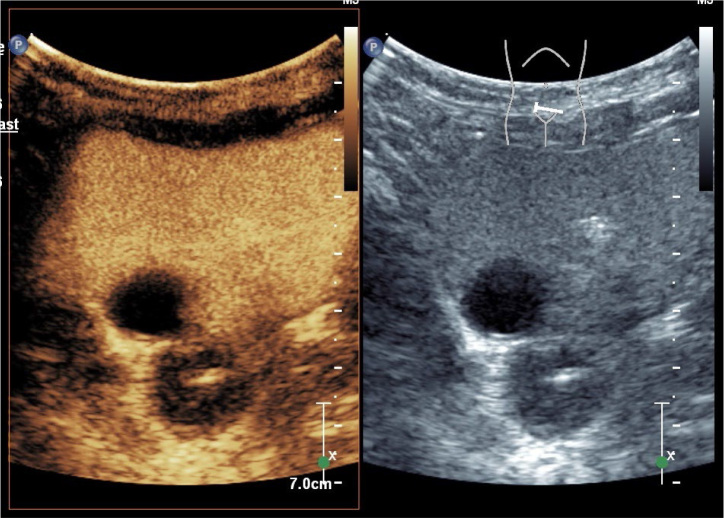

Conclusions: RBUS effectively diagnoses duplex kidneys with renal pelvic dilation, while ceVUS can further elucidate whether reflux occurs in the upper or lower moiety in cases of duplex kidneys with VUR. Compared to VCUG, both RBUS and ceVUS provide more intuitive diagnoses for duplex kidneys with VUR and ureterocele. Additionally, there is good consistency between ceVUS and VCUG in grading VUR. CeVUS is recommended as an initial evaluation method for patients suspected of having duplex kidneys associated with urinary tract infections.

Abstract Image